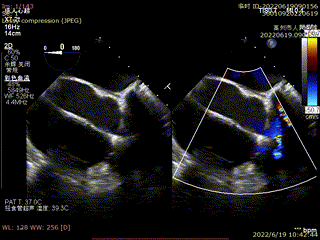

心脏彩超:三尖瓣关闭不全,收缩期可见极大量反流,VC>20mm,EROA:1.56cm²,反流峰速3.1m/g,压差33mmHg,三尖瓣反流5+。

术前TEE提示三尖瓣极重度反流

食管中段RV inflow-outflow引导前叶及隔叶分别捕获

术后超声显示反流基本消失